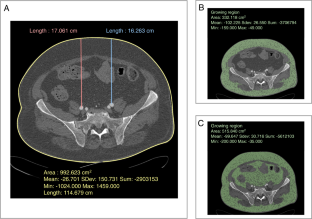

This study aimed at developing scores predicting surgical complications in obese transplant recipients, based on preoperative computed tomography (CT) parameters. All consecutive patients with a body mass index (BMI) ≥ 30 kg/m2 who underwent kidney transplantation between 2012 and 2019 were included. The preoperative CT parameters were assessed: total fatty surface (TFS), subcutaneous fatty surface (SFS), iliac vessel to skin distance (VSD), and abdominal perimeter (AP). Per- and postoperative complications (vascular, urinary, parietal, and digestive complications) within 30 days were listed. Predictive models of surgical complications were generated based on the results of the logistic regression. Among the 163 patients included, 53 (32.5%) experienced surgical complications. The AP was a risk factor for complications in multivariate analysis (OR: 1.050; 95% CI: 1.016–1.087; p = 0.03). Two predictive models of complications were created based on the statistical analysis: a one-variable model based on AP (sensitivity 86.8%, specificity 41.8%, area under the curve (AUC) 65.3, with a cutoff value of 107 cm) and a five-variable model based on BMI, TFS, SFS, VSD, and AP (sensitivity 73.6%, specificity 57.3%, AUC 66.2). These models, based on patient morphometric measurements, could allow predicting the occurrence of surgical complications in obese candidates for kidney transplantation.